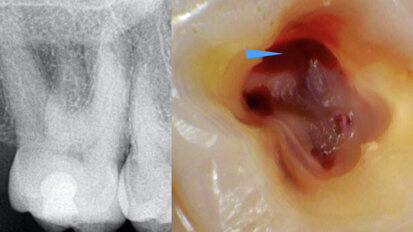

Management of iatrogenic pulpal floor perforation in a mandibular molar with MTA and PRF

This was a challenging case with the combined issues of a failed root canal therapy and an iatrogenic perforation of the floor of the pulp chamber. Though ...